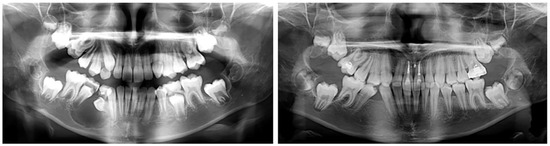

2.2.1. Clinical Case 1–Ectopic Eruption of Lower Right Lateral Incisor

The first clinical case is that of an 8-year-old girl with an ectopic eruption of the lower-right lateral (42) in the area of the first temporary molar. In the lower dental arch, the temporary right lateral incisor and canine are in preserved positions. After an X-ray examination, hypodontia of the upper laterals was established in the upper dental arch. A well-developed and normally positioned germ of right canines and premolars in the lower was found (Figure 1). In this early phase of mixed dentition, the ectopically erupted lower-right lateral incisor should be positioned in its normal location. This will prevent future canine transposition or canine retention due to the mechanical barrier that the lateral presents. At the same time, it is important to preserve the perimeter of the dental arch in the case of the premature exfoliation of the temporary canine.

Figure 1. Oral clinical status and X-ray examinations of a patient with an ectopic eruption of the lower-right lateral (42) in the area of the first temporary molar. The blue arrow show the natural position of lower right lateral incisor.